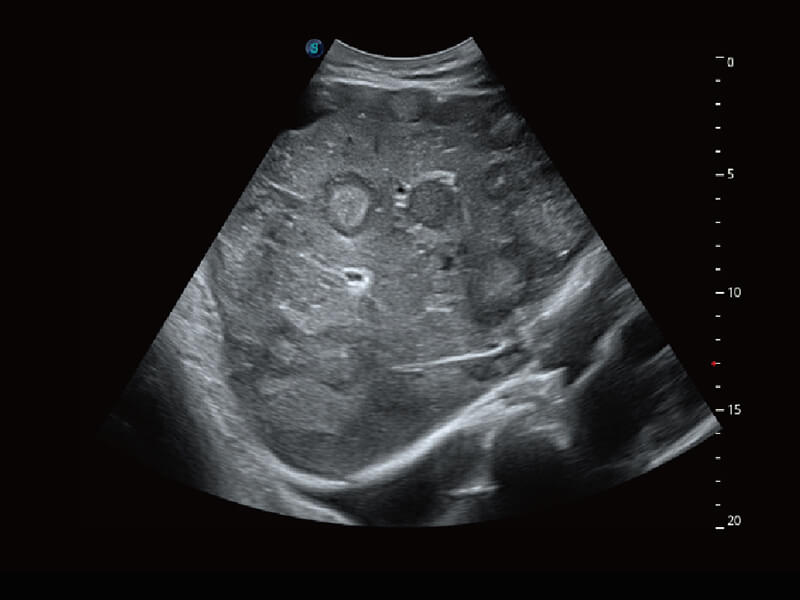

性能优异的硬件架构,极大提升超声系统的运行效率和数据处理能力。相比以往超声成像系统,Wis+平台为您带来极快的响应速度和成像帧频,提升检查流畅度。

S60探头工艺,从前端信号处理每一个环节采集无损声学数据,真实还原组织原貌,再现解剖细节。